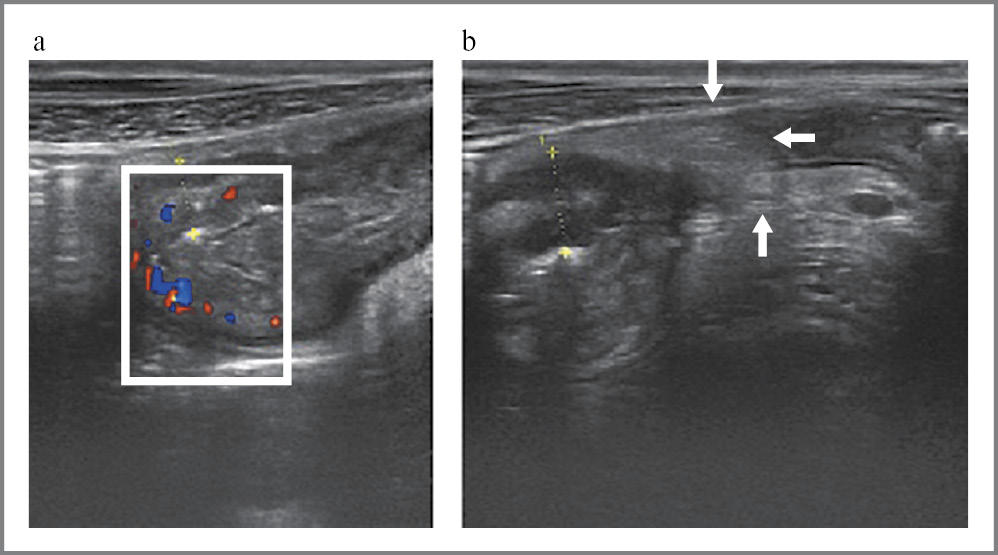

При обострении БК УКС выявлено у 63 (98%) пациентов, медиана ТКС составила 4,9 [3, 8; 6, 6] мм, что было выше, чем у пациентов в ремиссию БК (3,18 [2, 6; 3, 5]; p = 0,0001). Характерные УЗ-изменения представлены на рис. 4. В зависимости от выраженности активности БК определено УКС (табл. 3): так, при тяжелой атаке значение ТКС (8,55 [7, 53; 9, 63] мм) выше, чем при среднетяжелой (4,65 [3, 9; 6, 2] мм; р = 0,009) и легкой (4,08 [3, 5; 5, 68]; р = 0,00008). При этом в ремиссию БК УКС выявлено у 6 (60%) пациентов.

Рис. 4. Эхограмма пациента 35 лет с илеитом БК: a – визуализируется УКС подвздошной кишки до 7 мм (за счет подслизистой и мышечной оболочки), суживающее просвет кишки, при допплерографии определяется выраженное усиление кровотока; b – при поперечном срезе по периферии подвздошной кишки отмечается воспалительный «наползающий» брыжеечный жир.

Примечание. Эхограмма из личного архива авторов.

Fig. 4. Ultrasound imaging of a 35-year-old patient with CD sigmoiditis: a – in the ileum wall thickening is about 7 mm (due to the submucosa and muscular propria), intestinal lumen is narrowed, Dopplerography reveals increased blood flow; b – in a transverse section along the periphery of the ileum, inflammatory “creeping” mesenteric fat is noted.